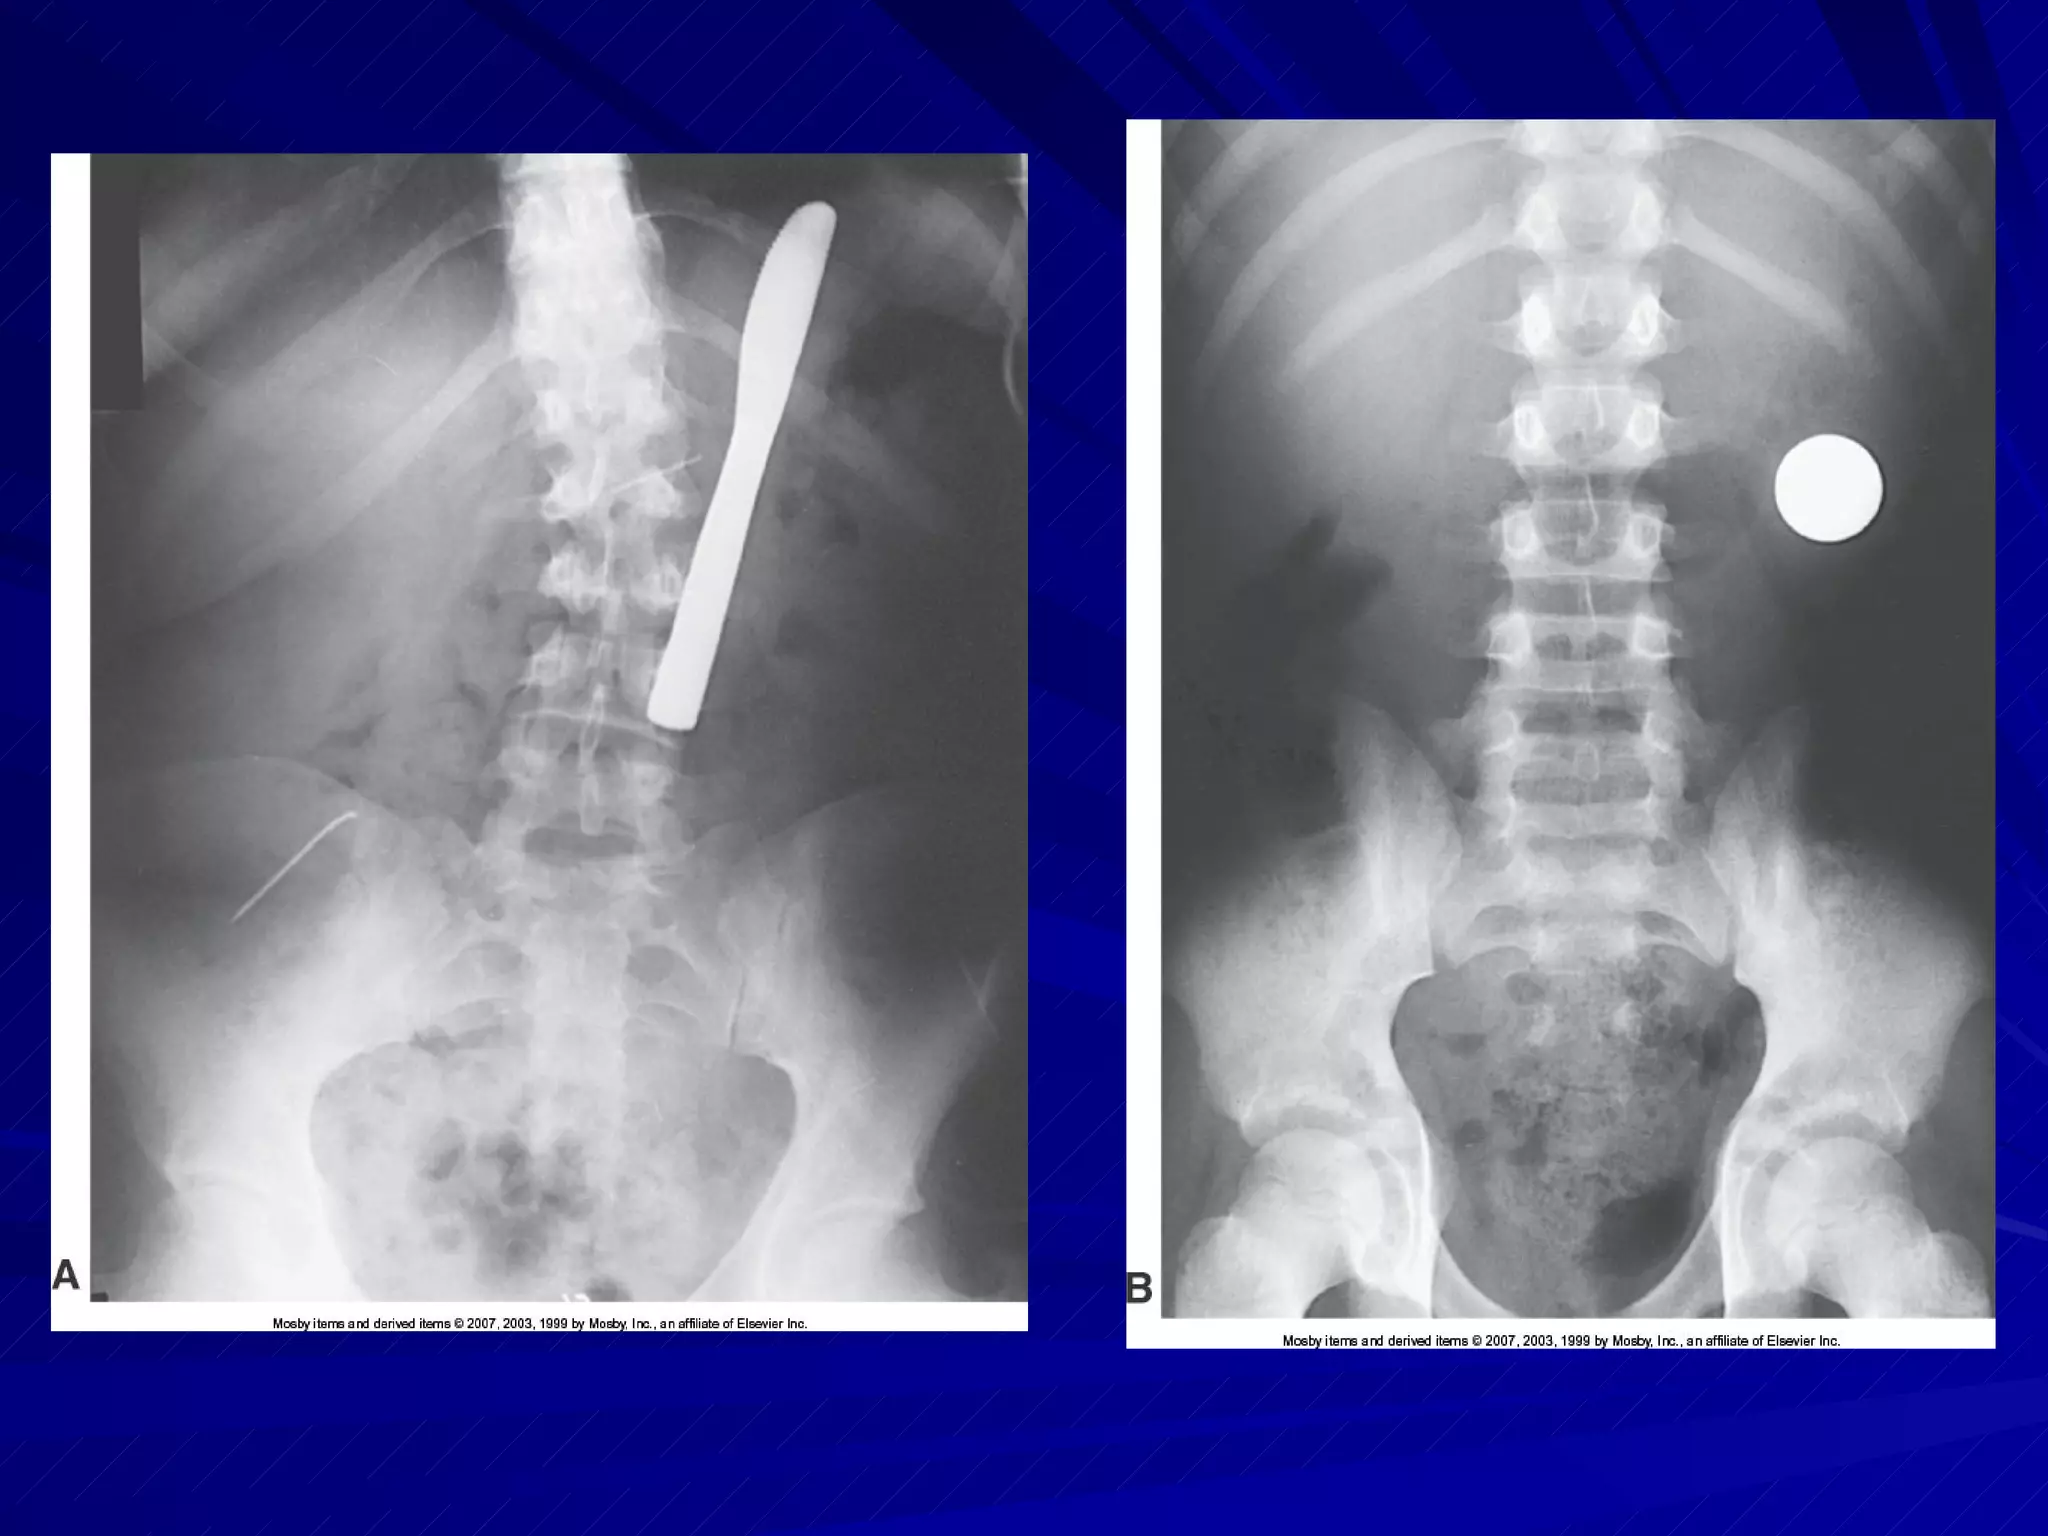

ID Markers Right or left side markers must be included on each image Other required ID markers must be in the blocker or elsewhere on the final image Markers used for penetrating trauma to identify entrance and exit wounds

Abdomen If transfer to x-ray table is not possible, obtain lift help for IR placement IR centered to MSP at level of iliac crests Check for possibility of fluid accumulation in abdominal cavity Affects exposure factors Requires close monitoring of patient for status change during procedures

Abdomen Mark entrance and exit wounds, if present Align shoulders and hips in same plane MCP parallel to table CR perpendicular to center of IR Image demonstrates entire abdomen with pubic symphysis visible at lower border

ID Markers Rightor left side markers must be included on each image Other required ID markers must be in the blocker or elsewhere on the final image Markers used for penetrating trauma to identify entrance and exit wounds

Abdomen If transferto x-ray table is not possible, obtain lift help for IR placement IR centered to MSP at level of iliac crests Check for possibility of fluid accumulation in abdominal cavity Affects exposure factors Requires close monitoring of patient for status change during procedures

Abdomen Mark entranceand exit wounds, if present Align shoulders and hips in same plane MCP parallel to table CR perpendicular to center of IR Image demonstrates entire abdomen with pubic symphysis visible at lower border